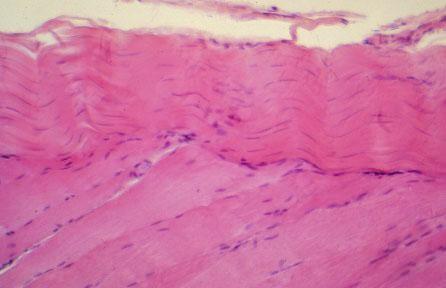

V-63 (4) Slide 15, Muscle-Tendon Junction (H&E). Muscle (bottom) is striated with euchromatic, elongated nuclei. Fibrocyte nuclei (top) of tendon are thin and slender, and heterochromatic; note the tendon consists of dense regularly arranged connective tissue (collagen, type I) which is extracellularly located.